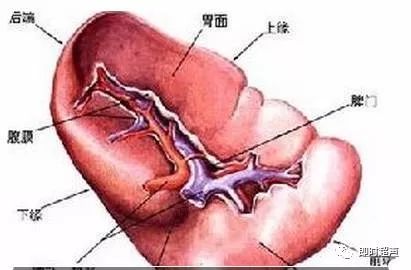

脾脏位于左上腹部,第9-11肋间腋前线至腋后线之间,上极在脊柱左侧2-4cm处。呈长椭圆形,分为膈面与脏面。膈面光滑隆起,紧贴膈肌与侧胸壁;脏面向内凹陷,其内下方与胃底相邻,其下方与左肾和结肠脾曲靠近。中部为脾门,有血管和神经出入,组成脾蒂。胰尾常抵达脾门附近。脾动脉沿胰腺上缘迂曲行走至脾门附近处分成4-7个分支进入脾脏,脾动脉直径约4-5mm,进入脾实质后分为前支及后支。脾静脉在脾动脉下后方,在脾门处由3-6个较大分支静脉汇合而成,沿胰腺上后方行走,呈轻度弯曲状,直径约5-8mm。

图1 脾脏正常截屏

正常脾脏的肋间斜切声像图呈新月形,包膜薄而光滑,外侧缘呈向外突的弧形,内侧缘中部向内凹陷,为脾门。脾门区可见脾静脉的管状无回声区。脾动脉较细常显示不清。正常脾实质呈均匀细小的点状回声,回声较低,一般稍低于正常肝组织的回声。